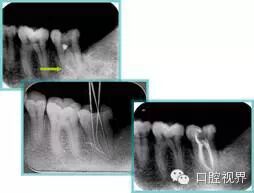

共有 4 张 X 线片,分别是术前、诊断丝 、主牙胶尖确认、术后。

( 1 )术前:术前 X 线片用来了解牙齿的大概情况。术前预期为多根牙时 X 线片应偏头拍摄。

( 2 )诊断丝:根据术前 X 线片进行开髓、根管的初步预备后,需要插入诊断丝,用来指示工作器械位置。常用 10 号或 15 号扩大器作为诊断丝插入牙髓腔。

( 3 )主牙胶尖确认:通过术前预期和诊断丝诊断,明确工作长度、牙根走向,进行根管预备。之后应进行主牙胶尖(中锉)确认,已明确根管是否适合充填。

( 4 )术后:观察治疗效果。